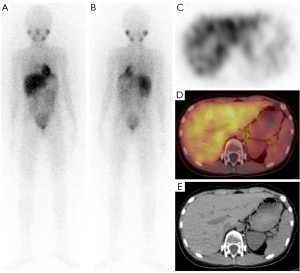

Our study showed the clinical significance of 123I-MIBG scintigraphy in distinguishing between patients with and without metastasis, and its superior diagnostic efficacy (AUC: 0.760). Consistent with previous reports, our study reported a specificity rate of 94.4%, but a sensitivity of only 57.5%, which was slightly lower than that reported in previous studies. However, Liu et al. reported a sensitivity of 61%, which is consistent with our findings. The difference in sensitivity could be attributed to: (I) the limited resolution; (II) the presence of small lesions near the site of physiological MIBG uptake; and (III) myelosuppression after chemotherapy (30). For example, among the 123I-MIBG negative patients, there was one case in which 123I-MIBG scintigraphy produced a false-negative result; however, this might have been due to the close proximity between the time of the child’s chemotherapy and the scan, which were only 14 days apart (Figure 3).

The limitations of 123I-MIBG scintigraphy, which include its unsuitability for dynamic testing due to radioactivity and its cumbersome procedure that requires at least two days scheduling, as well as the occurrence of false-negative scans, primarily in MRD (+) subjects following chemotherapy and/or surgery (38), necessitates the development of new methods to diagnose recurrence and metastatic in NB patients. Figures 3,4 show the high sensitivity of 123I-MIBG and MRD, respectively. It is important to note that while the model enhanced the sensitivity of MIBG, this improvement came at the cost of reduced specificity. Other factors in the model might have contributed to this decrease in specificity.